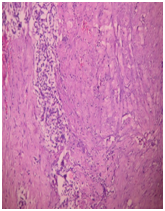

Intra operatively there were wide BP fluctuations (from 50 to 210 mm Hg Systolic). Direct vascular connections from right common iliac artery and venous tributaries to IVC were ligated. Tumor was removed en-bloc. Post operatively maintained the blood pressure with tapering of alpha blockers. Patient had an uneventful post-operative recovery. The histopathology of the specimen confirmed the diagnosis of Paraganglioma (Figure 1-7).

Figure 7 Histopathology - Paraganglioma.